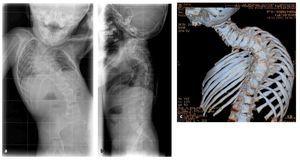

La indicación para la intervención fue en 16 casos una escoliosis congénita (figs. 24a-24c), en once casos una escoliosis neurológica y en doce casos una EIP. Las curvas se determinaron según Cobb. El ángulo de Cobb antes de la intervención medía un promedio de 65º (45-130º), y después de la intervención, un promedio de 32º (25-75º). En 18 pacientes tratamos una escoliosis torácica, en 18 pacientes una toracolumbar y en tres pacientes una lumbar (mielomeningocele). En 18 casos se utilizó un implante «costilla a costilla», en cinco casos un sistema de barra doble hasta la pelvis y en 18 casos un sistema híbrido (figs. 25 y 26).

Figuras 25a a 25c. a) Radiografía preoperatoria en proyección anteroposterior de una EIP con un ángulo de Cobb de 86º. b) Radiografía postoperatoria de una instrumentación «costilla a CL» realizada en una escoliosis toracolumbar progresiva. c) Radiografía postoperatoria en proyección anteroposterior después de 5 años. La curva se mantiene flexible y con buena corrección.

Figuras 26a y 26b. a) Radiografía postoperatoria en proyección anteroposterior después de corregir una escoliosis congénita mediante la técnica híbrida. b) Radiografía lateral postoperatoria.